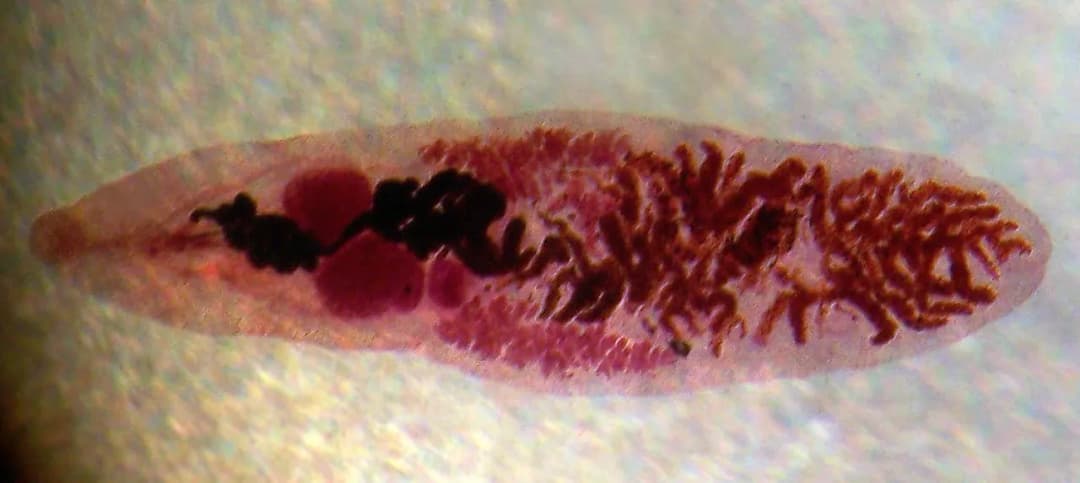

Odkryj, jakie badania na robaki pomogą Ci wykryć pasożyty jelitowe. Poznaj skuteczne metody diagnostyczne, od tradycyjnych po nowoczesne, i dowiedz się, kiedy warto je wykonać. Zadbaj o swoje zdrowie już dziś!

Odkryj metody wykrywania pasożytów we krwi. Dowiedz się, jakie badania krwi na pasożyty są najskuteczniejsze, jak się do nich przygotować i co oznaczają wyniki. Chroń swoje zdrowie już dziś!